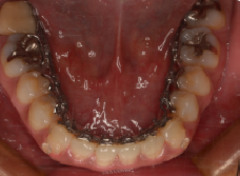

裏側矯正(メリット・デメリット)

裏側矯正のデメリット

④装置を付ける前でも、表より裏側の方が歯磨きがしづらいのでさらに、磨くのが難しい